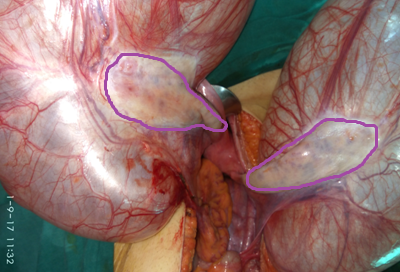

Both cystadenomas were excised with preservation of both ovaries (Courtesy Dr. V. Penopoulos)